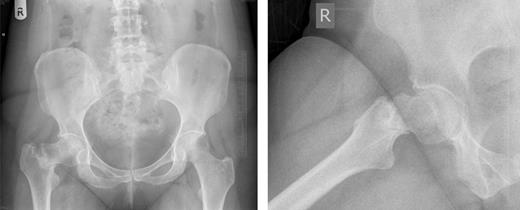

Anterior-posterior and lateral radiographs taken 6 months postoperatively demonstrating union of the fracture and osteotomy site.